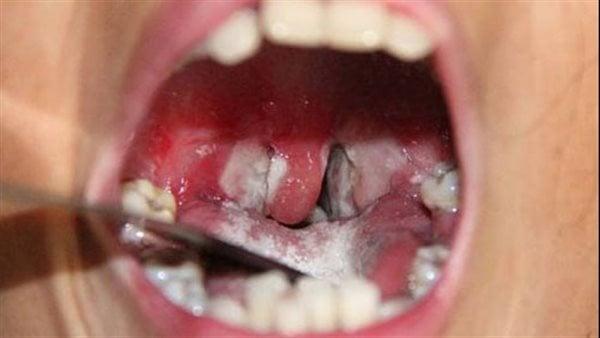

وفاة 7 أشخاص ببلدية تناها وإغلاق الأسواق الأسبوعية بسبب "الدفتيريا"

أفادت مصادر محلية ان سبعة  أشخاص توفوا ببلدية تناها بمقاطعة كنكوصة في ولاية العصابة، وذلك جراء إصابتهم بمرض يرجح أنه الدفتيريا، فيما أصيب أكثر من 70 آخرين.